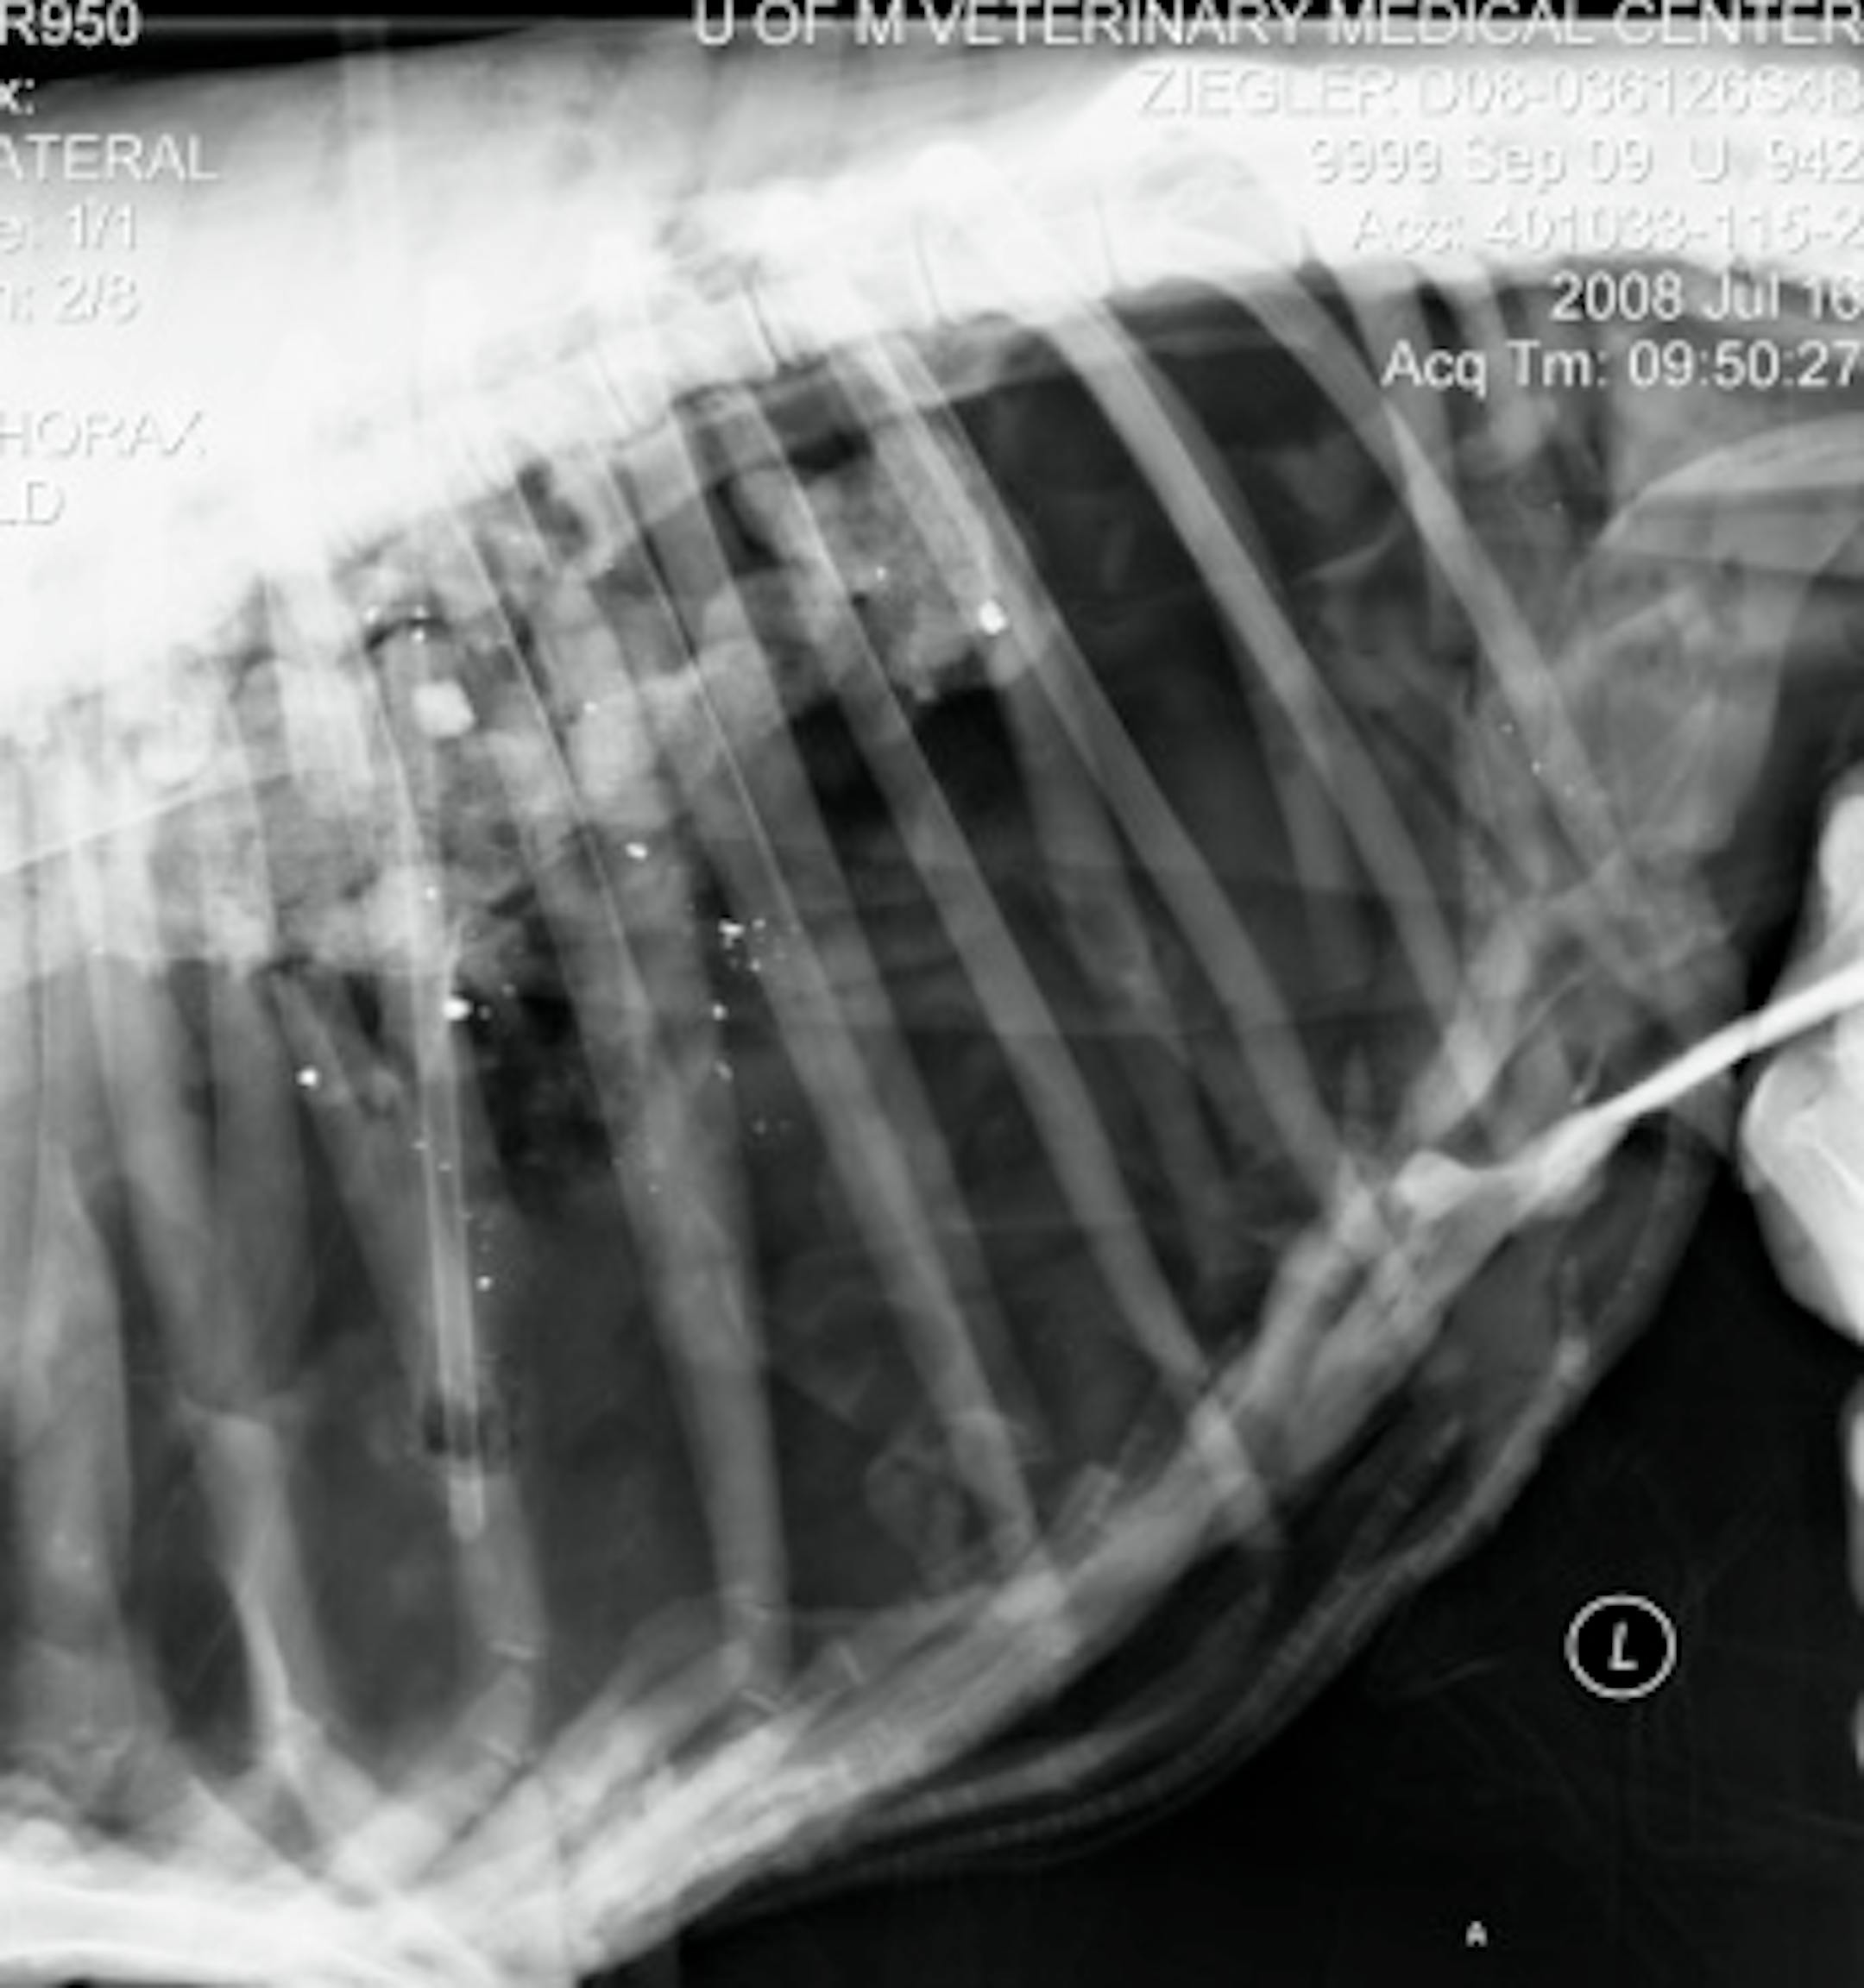

White specks on this x-ray of a sheep are lead bullet fragments, part of a DNR ballistic study. The study showed that some lead bullets fired from high-powered rifles fragment greatly, which has implications for deer hunters.

Lead was found up to 18 inches from wound channels in a study on sheep conducted by the DNR in July, said Lou Cornicelli, DNR big game program leader. The sheep, euthanized first, are anatomically similar to white-tailed deer.

Ballistic-tip bullets, made to rapidly expand on impact, fragmented the most. They averaged 141 fragments per carcass, with an average maximum distance of 11 inches from the wound channel.

Soft-point bullets and bonded lead-core bullets with exposed lead cores had an average of 86 and 82 fragments, respectively, also with a maximum distance of 11 inches.

Shotgun slugs and muzzleloader bullets fragmented far less than lead bullets fired by high-powered rifles. Still, shotgun slugs left an average of 28 fragments at an average maximum distance of 5 inches from the wound. About 25 percent of the state's firearm harvest falls to shotgun slugs.

Several types of bullets were shot from different firearms into 72 dead sheep in July. X-rays and other equipment were used to examine for bullet fragmentation.